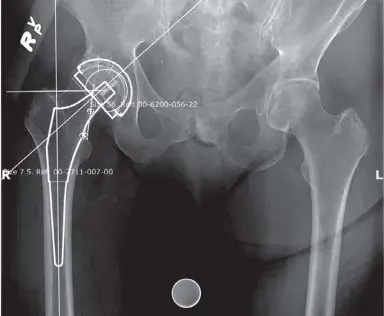

- التخطيط المسبق للجراحة (Templating): باستخدام هذه الصور، يقوم الأستاذ الدكتور محمد هطيف بإجراء تخطيط دقيق قبل الجراحة (كما هو موضح في الشكل 6.1). يتضمن ذلك تحديد حجم وموضع المكونات الاصطناعية (رأس الفخذ والحُق) التي سيتم استخدامها، مما يضمن أفضل ملاءمة واستقرار للمفصل الجديد.

الشكل 6.1: بيانات التخطيط المسبق للجراحة مع صورة أشعة سينية للورك المخطط له

- التخطيط المسبق: يتم التخطيط المسبق الدقيق وتحديد حجم المكونات (Templating) على صور الأشعة السينية الأمامية الخلفية للحوض والصورة الجانبية للورك (كما هو موضح سابقًا في الشكل 6.1).